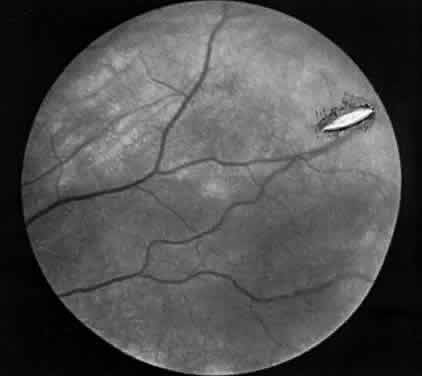

Hemorrhage initially covers the perforation site. Some of this hemorrhage may break through into the vitreous cavity but usually remains confined to the choroid and retina. In a day or two, bare sclera becomes visible, usually surrounded by residual hemorrhage and a rim of light pigmentation.19 It appears as if the choroid and the retina were scooped out, leaving bare sclera behind (Fig. 1). Inverted cutting needles seem responsible since this is a complication almost unheard of before or after their common use. Prophylaxis indicates the use of a needle that is not sharp on the convex curve. The management of these perforations remains controversial.20 In our experience, widely dilating the pupil permits nearly immediate diagnosis as the area can be clearly seen through the usually clear media. Depending on the characteristics of the perforation, transpupillary laser coagulation or direct cryotherapy can be administered easily. Some suggest, however, that observation without treatment is all that is required since the perforations are almost always self-sealing and result in no significant sequelae. Nevertheless, in a series of 728 patients with known scleral perforations, 14 (2%) of the cases had a retinal detachment and eight resolved without complications.21